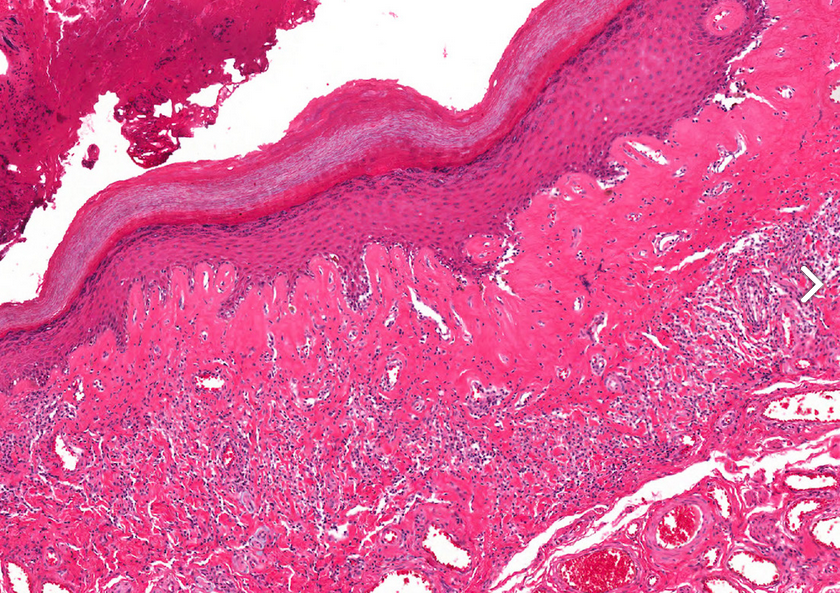

Classic or band-like lichen sclerosis

Features: Sclerotic band replacing the LP is located between the epithelium and a dense and diffuse lymphocytic infiltrate located below.